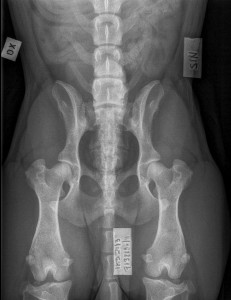

Kusti (Big-Wood’s Gruffud Gritus for Kilvroch) is hip scored in UK. His KC/BVA scores are 8:6=14. Thank you Eileen for your interest to x-ray him. Kusti (Big-Wood’s Gruffud Gritus for Kilvroch) on lonkkakuvattu uudessa kotimaassaan Englannissa. Tulokset olivat mukavaa luettavaa. Oikea lonkka sai numeeriseksi arvokseen 8, vasen 6 ja kokonaisluku 14 on cardiganille varsin kelpo luku. …